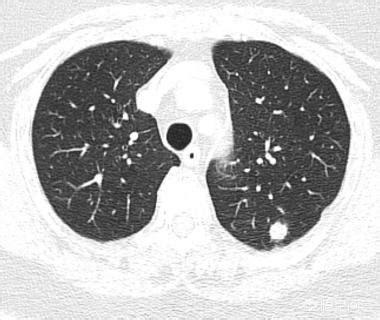

Les nodules pulmonaires sont avant tout des ombres des poumons ≤ 3cm, s'ils sont > 3cm ils sont appelés masses. Les nodules pulmonaires sont généralement classés, en fonction de leur densité, en nodules solides et sub-solides (c'est-à-dire en nodules de verre pilé). Les nodules pulmonaires peuvent être solitaires (c'est-à-dire un) ou multiples (c'est-à-dire plus d'un). Avec la popularité du scanner spiralé multicouche, de plus en plus de nodules pulmonaires asymptomatiques ont été découverts, et de nombreuses personnes s'inquiètent de savoir s'il s'agit d'un cancer du poumon, mais en fait, il n'y a pas lieu de s'inquiéter, la plupart d'entre eux sont bénins, et seul un petit nombre d'entre eux est un cancer du poumon.

Les nodules pulmonaires sont généralement détectés par radiographie (radiographie du thorax) ou par tomodensitométrie, principalement par tomodensitométrie, car de nombreux petits nodules ne sont pas du tout visibles sur une radiographie du thorax et doivent être détectés par une tomodensitométrie du thorax. C'est ce que se demandent de nombreuses personnes qui font la une des journaux : pourquoi n'y a-t-il rien à redire aux examens médicaux annuels et, soudain, un cancer du poumon se déclare-t-il ? On suppose que l'examen physique a été effectué à l'aide d'une radiographie du thorax plutôt que d'un scanner. Par exemple, si l'on veut voir s'il y a des lésions substantielles (excroissances) dans le foie ou les reins, il faut faire une échographie ou un scanner, et si l'on veut voir les lésions gastro-intestinales, il faut faire une gastroscopie ou une coloscopie, et pas seulement des tests de laboratoire tels que des analyses de sang et d'urine, mais beaucoup de lésions peuvent être normales dans les tests de laboratoire. Ainsi, pour détecter de petites lésions précoces dans les poumons, ou des lésions précancéreuses, en particulier des nodules de verre dépoli, il est recommandé d'effectuer un scanner hélicoïdal à faible dose.